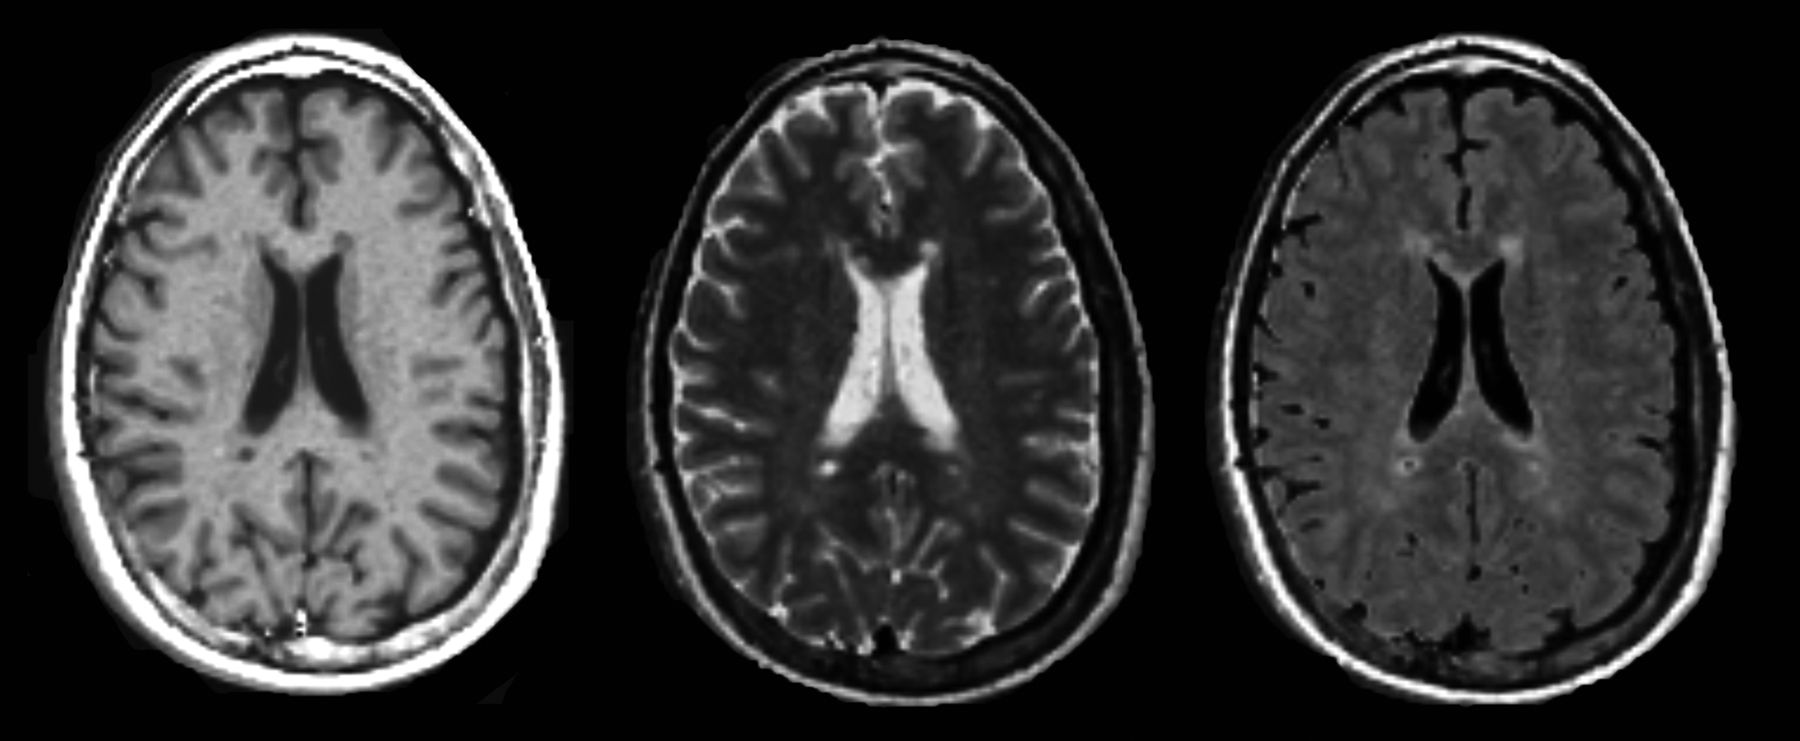

The qMRI sequence yields quantitative maps of R1, R2, and PD (Fig 1), which are used for measurements and to create synthetic images matching the conventional ones (Fig 2). The postprocessing time of the raw image dataset was approximately 1 minute on an ordinary PC by using SyMRI Diagnostic software (SyntheticMR, Linköping, Sweden) to create the synthetic images. Relaxation time values (T-values) were obtained from R1 and R2 by calculating T = 1/R. Using the software MevisLab, Version 2.4 (MeVis Medical Solutions, Bremen, Germany), we anonymized the synthetic images with corresponding conventional images and presented them to a neuroradiologist in random order. For each patient, synthetic T2-weighted, T2-FLAIR, T1-weighted, and T1-weighted Gd images were displayed side by side. MS lesions were identified by conventional neuroradiologic criteria, described in the McDonald criteria for MS. The MS lesions were then classified by visual assessment as enhancing or nonenhancing. The neuroradiologist had access to the conventional images for confirmation of the findings (Fig 3A).

Synthetic T1WI (left), T2WI (middle), and T2-weighted FLAIR (right) imaging, postsynthesized from the quantitative MR imaging scan in a patient with MS.